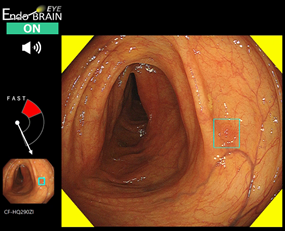

サイバネットシステム(株)(以下「サイバネット」)は,昭和大学横浜市北部病院消化器センターの工藤進英教授,名古屋大学大学院情報学研究科の森健策教授らのグループと共同開発したAIを搭載した大腸内視鏡画像診断支援プログラム「EndoBRAIN-EYE®(エンドブレインアイ)」について,改正薬機法の新制度「医療機器の特性に応じた変更計画の事前確認制度(通称:IDATEN制度)」の承認を取得した。

EndoBRAIN-EYEは,国内5施設(昭和大学横浜市北部病院,国立がん研究センター中央病院,静岡県立静岡がんセンター,東京医科歯科大学医学部附属病院,公益財団法人がん研究会有明病院)が学習画像を提供し,名古屋大学大学院情報学研究科森健策研究室がAIエンジンを開発,サイバネットにより実装開発された医療機器ソフトウェア。大腸内視鏡で撮影された内視鏡画像をAIが解析し,ポリープなどを検出すると警告を発し,医師による病変の発見を補助する。本ソフトウェアはオリンパス社製の汎用大腸内視鏡に使用でき,多くの機種と組み合わせて使用することができる。